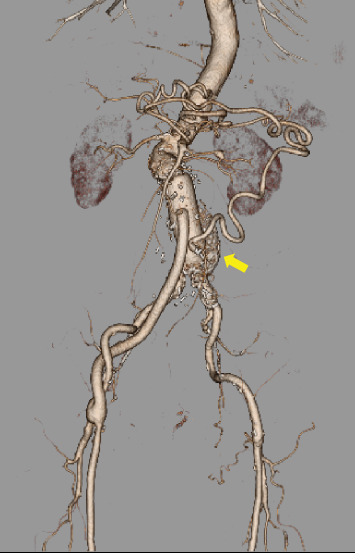

一名78岁男性被诊断为腹主动脉瘤伴肠系膜动脉弯曲。术中应用肠系膜下动脉灌注进行腹主动脉置换和肠系膜下动脉重建。将4-Fr动脉鞘插入左肱动脉,将10-Fr球囊导管插入肠系膜下动脉灌注。术中肠血流良好,患者术后病程良好。这种方法对于肠系膜动脉曲流患者的腹主动脉手术是一种简单有效的选择。

A 78-year-old man was diagnosed with an abdominal aortic aneurysm with a meandering mesenteric artery. We performed abdominal aortic replacement and inferior mesenteric artery reconstruction using intraoperative inferior mesenteric artery perfusion during surgery. A 4-Fr arterial sheath was inserted into the left brachial artery, and a 10-Fr balloon catheter was inserted into the inferior mesenteric artery for perfusion. The intraoperative intestinal blood flow was satisfactory, and the patient's postoperative course was favorable. This method was an easy and effective option for abdominal aortic surgery in patients with a meandering mesenteric artery.